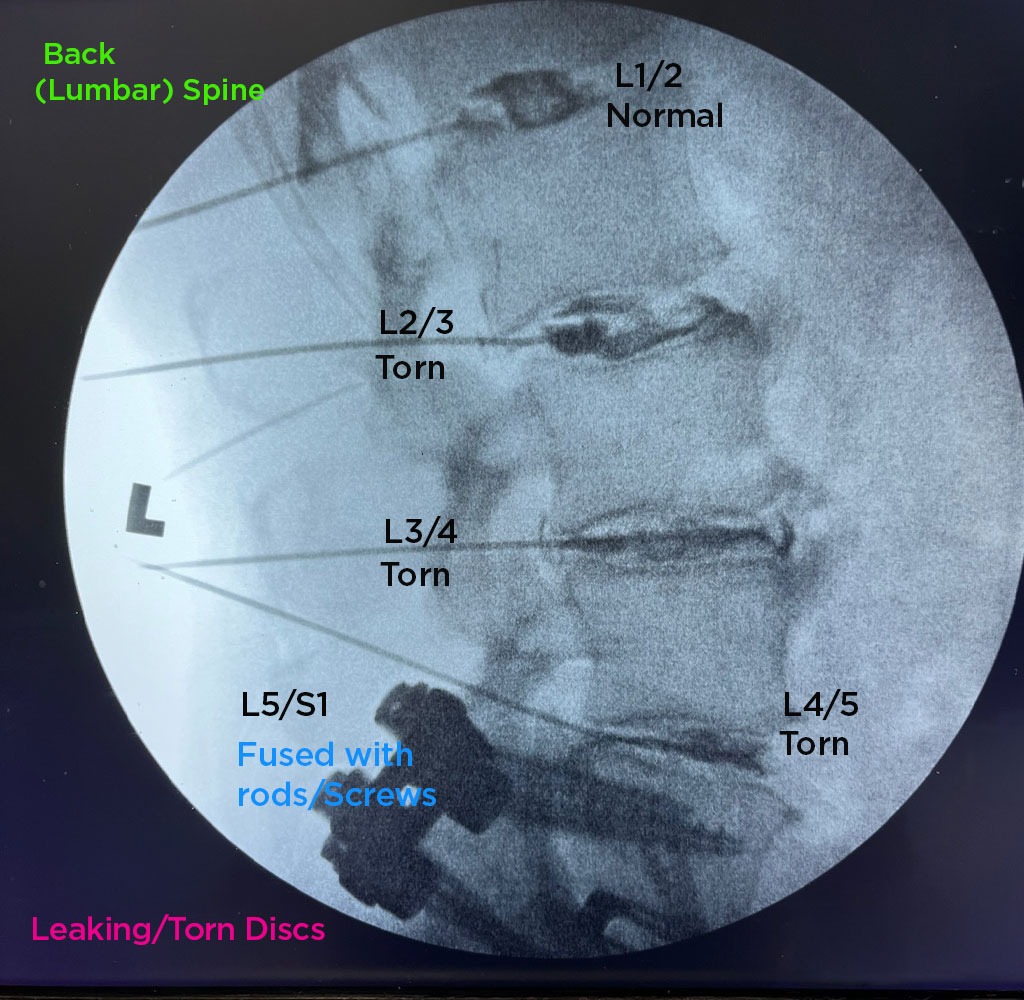

The Annulargram is a pain-free test and a crucial part of the DISCSEEL Procedure that identifies even the most subtle tears in spinal discs that MRI and discography cannot.

During the Annulargram, every disc in the region is tested to address current and future pain issues by finding even the most subtle annular tears. With the Annulargram, damaged spinal discs are pinpointed and precisely treated with Fibrin, leaving all healthy discs as they are.

Tears in spinal discs cannot be seen on MRI nor discography. As shown: leaky discs are only visible on the Annulargram.

The DISCSEEL Procedure is an option even if you have previously had spine surgery or regenerative procedures (stem cell or PRP) that have failed.